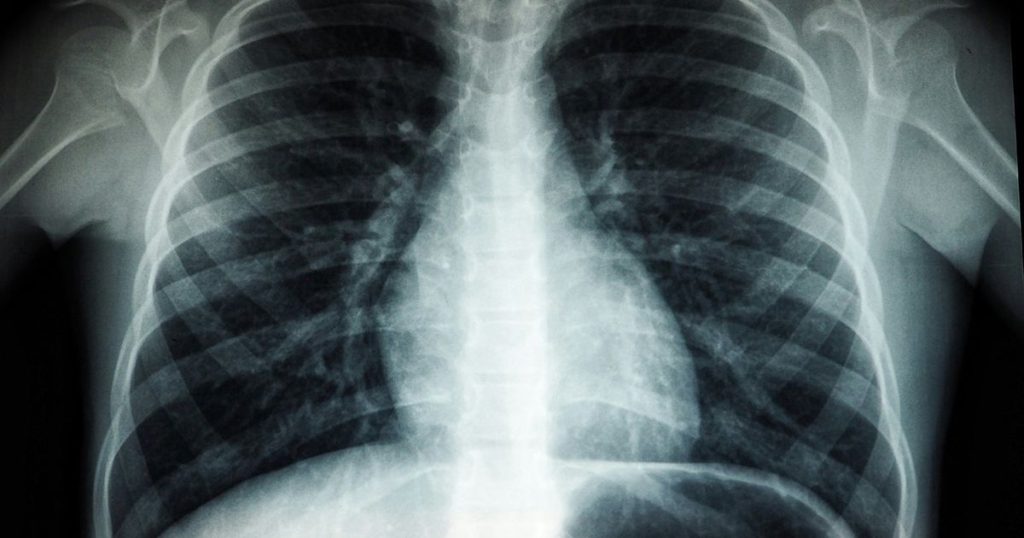

Duke research uncovers a new source of severe lung cancer, opening doors for groundbreaking treatments.

Duke Researchers Make Breakthrough in Understanding Lung Cancer A recent study from researchers at Duke University has significantly changed our understanding of one of the most lethal types of lung cancer. This Wednesday, the team published findings indicating that small cell lung cancer (SCLC) likely originates in basal stem-like cells instead of specialized lung cells […]